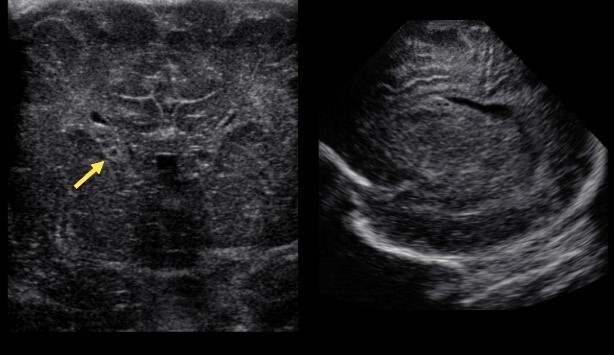

Neonatology Germinolytic Cyst 1 Image